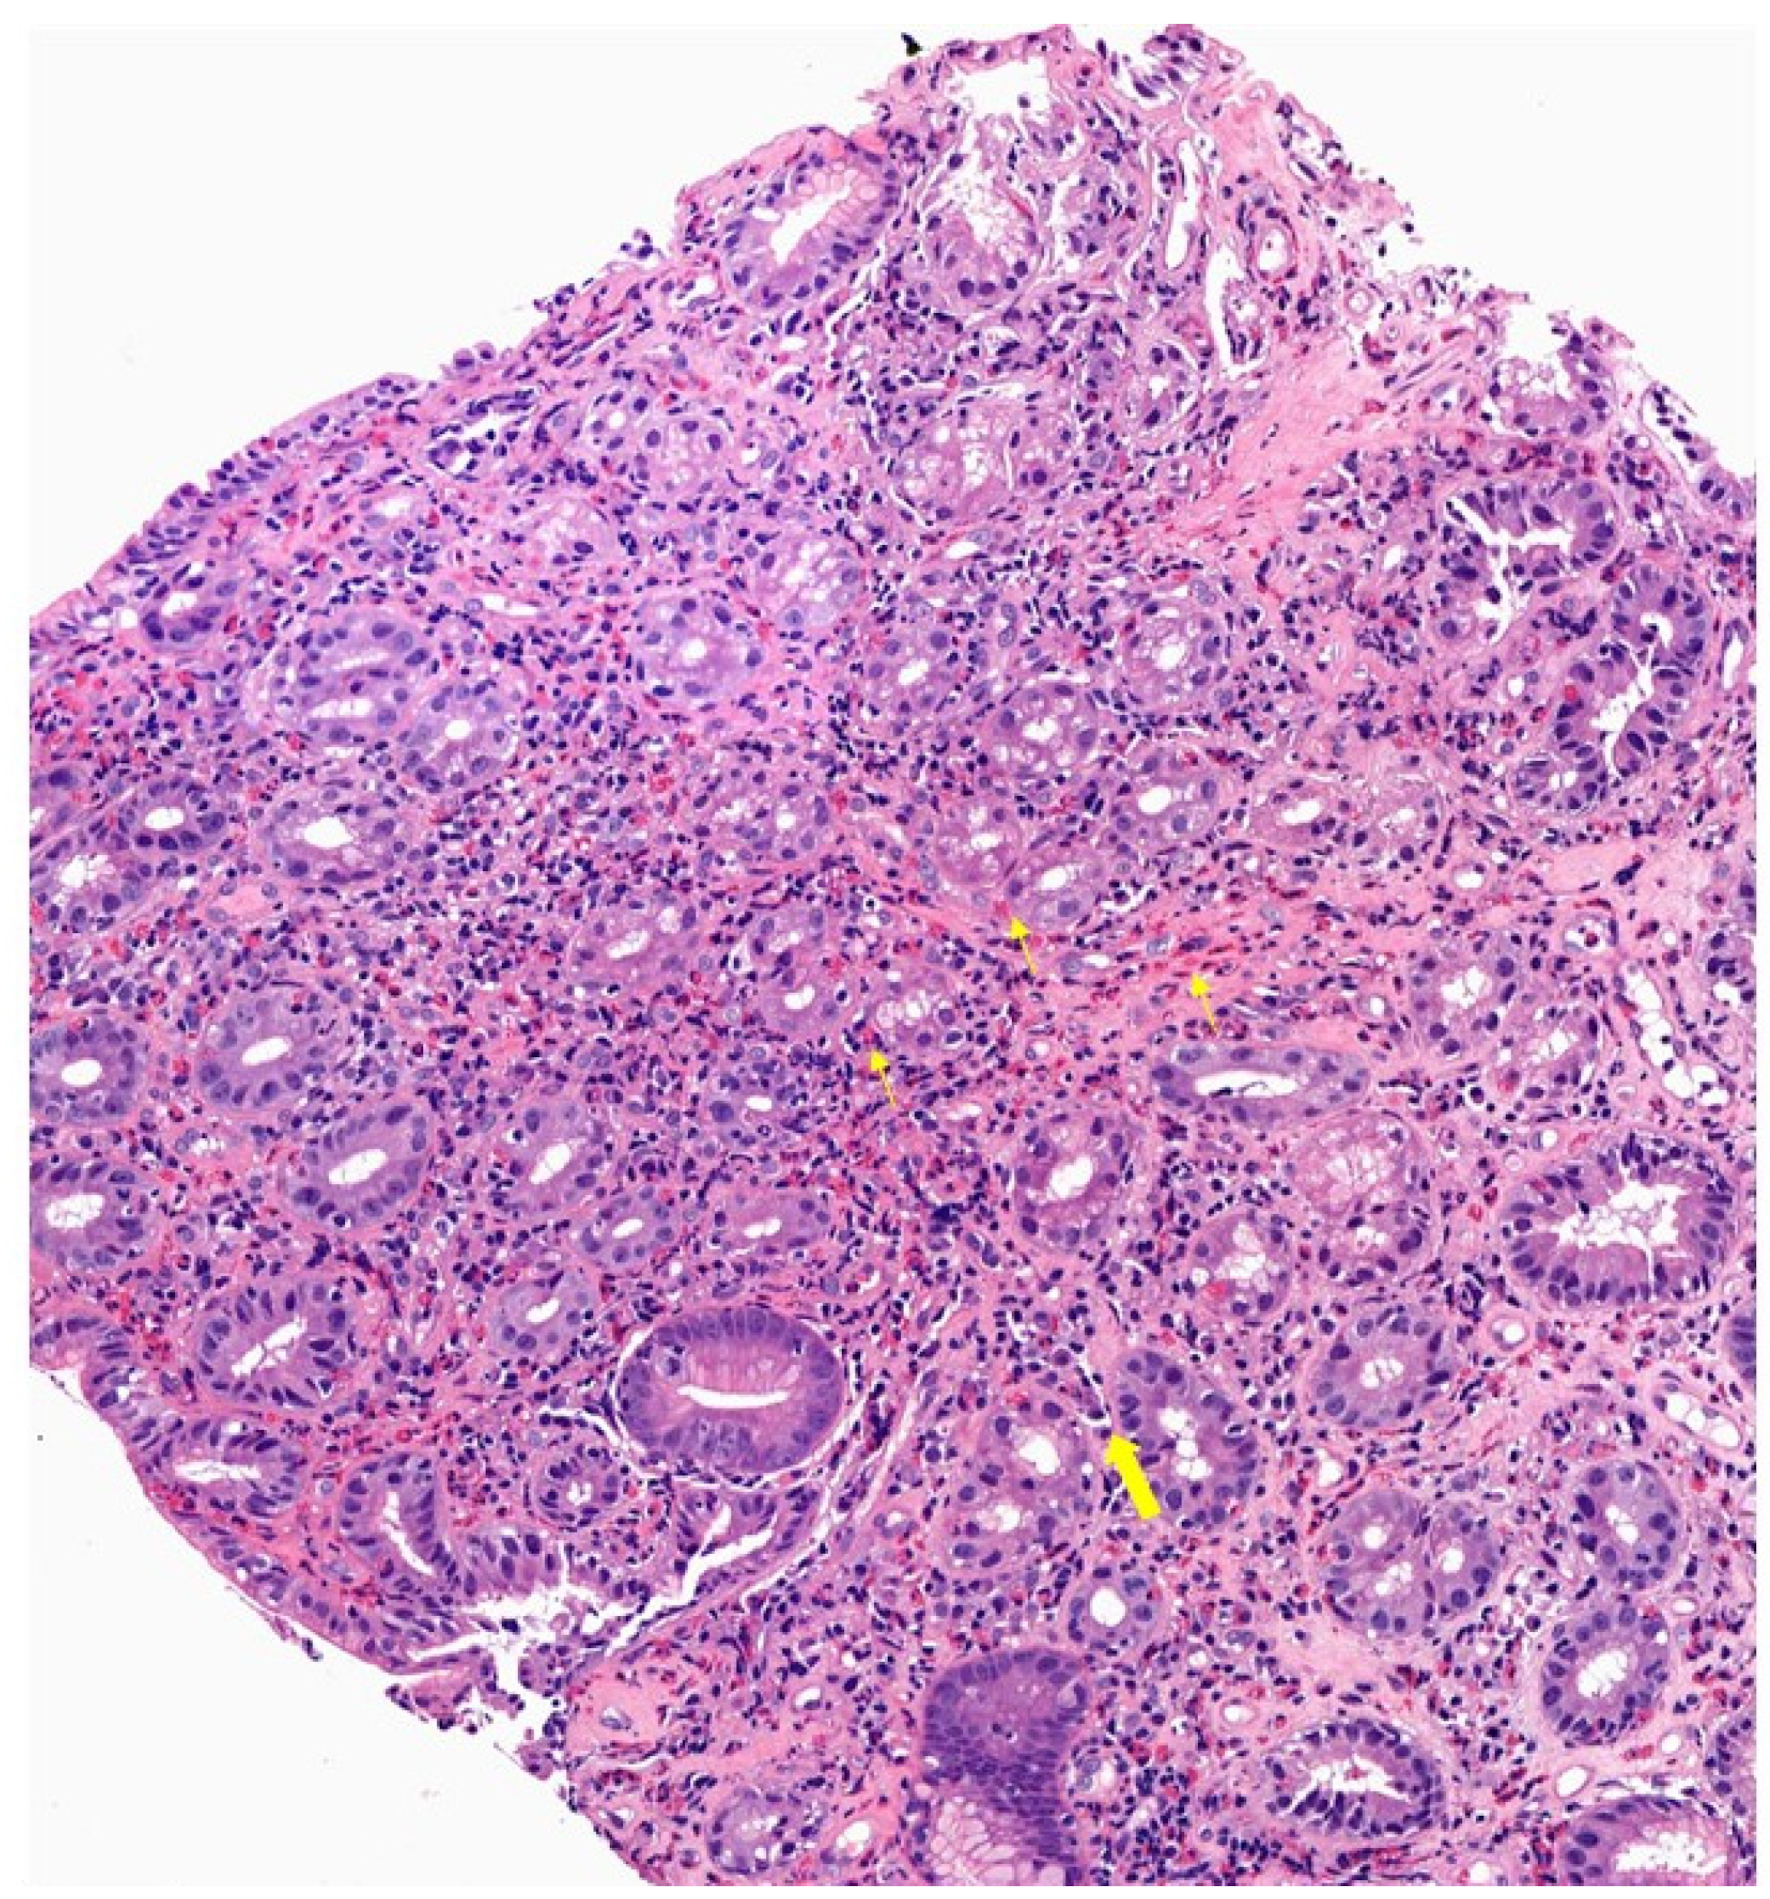

3.3. Histology

4.3. Histology